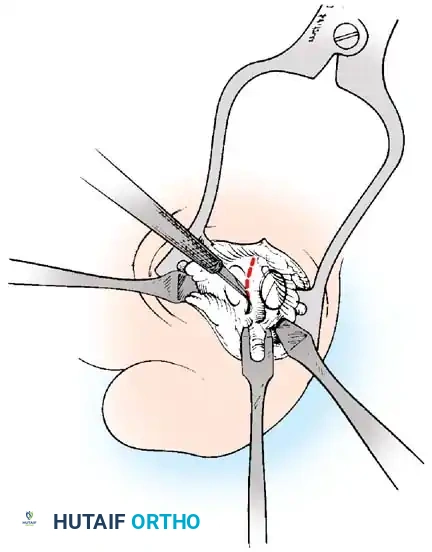

• Incise the intersesamoid ligament longitudinally with a No. 67 Beaver or No. 15 Bard-Parker blade. If tenotomy scissors are used, place one arm of the scissors under the ligament (this arm rests on the dorsal side of the fl exor hallucis longus) and the other arm dorsal to the ligament.

• When the intersesamoid ligament is incised, grasp the sesamoid fi rmly with forceps or a small Kocher clamp, fl ex the toe at the interphalangeal and metatarsophalangeal joints to relax the fl exor hallucis longus tendon, and pull the fi bular sesamoid distally and medially.

• With release of the intersesamoid ligament, the medial surface of the fi bular sesamoid is free from soft tissue. Distally, the sesamoid is free because of resection of the base of the proximal phalanx. This leaves two sides of the sesamoid, distal and medial, free of soft tissue.

• While pulling the sesamoid distally and medially, use a small blade to incise along the lateral margin of the sesamoid under direct vision. Keep pulling the head of the metatarsal dorsally and holding the hallux distracted and in fl exion. This greatly aids in identifi cation of the margins of the fi bular sesamoid, particularly laterally and proximally.

• The most diffi cult part of the sesamoidectomy and that which should be done last is release of the proximal lateral corner of the sesamoid where the fl exor hallucis brevis lateral head inserts. While incising the lateral capsular attachments to the sesamoid, do not bury the blade of the knife because the neurovascular bundle to the lateral side of the hallux is just lateral to the capsule.

• Now all attachments to the fi bular sesamoid have been removed except the lateral head of the fl exor hallucis brevis, which inserts on the proximal lateral margin of the sesamoid. This is a diffi cult section to remove; however, this section can be released under direct vision by pulling the sesamoid distally and medially and lifting the metatarsal head dorsally with a strong two-toothed retractor.

Fig. 78-31 Excision of fi bular sesamoid in modifi ed Keller procedure. With base of proximal phalanx removed and medial eminence excision, exposure of fi bular sesamoid is not as diffi cult from medial incision. A, Operative photograph showing elevation of fi rst metatarsal with strong two-tooth retractor and use of small osteotome to mobilize fi bular sesamoid and lateral capsuloligamentous (frequently contracted) structures. Osteotome is between metatarsal head and lateral sesamoid. When mobilization of fi bular sesamoid is complete, entire sesamoid is visible for excision. Note chondromalacia of tibial sesamoid articular surface medial to osteotome. B, Fibular sesamoid has been excised, and lateral capsular structures and conjoined tendon (in forceps) have been released. Neurovascular bundle to lateral side of hallux is adjacent to these structures. C, Diagrammatic representation of modifi ed Keller procedure. By excising fi bular sesamoid, valgus moment of conjoined tendon of fl exor hallucis brevis and adductor hallucis no longer pulls fl exor hallucis longus tendon laterally (carrying hallux with it) through capsulosesamoid plantar plate and pulley system. D, Metatarsal head must be lifted dorsally to excise fi bular sesamoid under direct vision. E, Note exposure of fi bular sesamoid after mobilization of metatarsal head. Continued